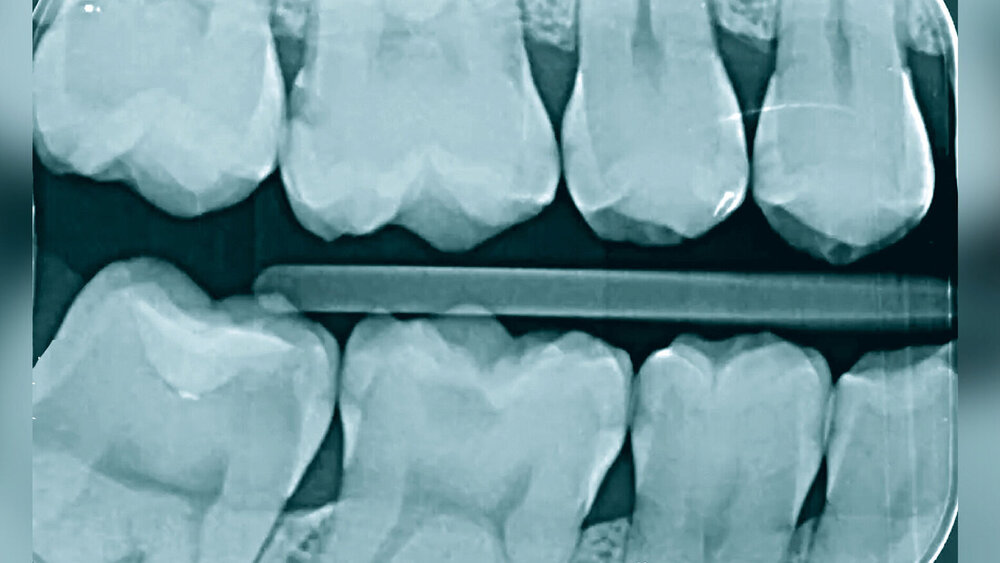

Guided Endodontics

Eine der großen Herausforderungen in der Endodontie ist die Vorhersagbarkeit bei Wurzelkanalbehandlungen. PD Dr. med. dent. Thomas Connert, Basel, stellte die „Navigierte Endodontie“ zur Behandlung von Zähnen mit obliterierten Wurzelkanälen und apikaler Parodontitis vor. Hauptursache für kalzifizierte Wurzelkanäle sei ein vorangegangenes dentales Trauma. Rund die Hälfte der deutschen Bevölkerung hat im Lauf ihres Lebens ein dentales Trauma. Bei rund 15 Prozent aller traumatisierten Zähne zeigt sich im Verlauf eine Obliteration, insbesondere nach einer Extrusion oder einer lateralen Dislokation, weniger bei einer Kontusion. Die Behandlung eines solchen Wurzelkanals stelle große Anforderungen an den Zahnarzt oder die Zahnärztin und gehe häufig mit Perforationen einher. Die technische Fehlerquote an Frontzähnen wird in der Literatur mit bis zu 70 Prozent angegeben. Connert führte mehrere Studien an, deren Ergebnisse zeigen, dass die Technik der „Guided Endodontics“ mittels Führungsschablone den Behandlungserfolg deutlich erhöhen kann.

Präzise und minimalinvasive Zugangskavitäten möglich

Den Workflow erklärte Connert detailliert: Nach der Indikationsstellung muss zunächst ein dreidimensionaler Datensatz (DVT) angefertigt werden sowie ein Intraoralscan erfolgen. Eine geeignete Software fusioniert dann die beiden Datensätze. Im entstandenen dreidimensionalen Modell kann nun eine digitale Zugangskavität geplant werden – mit dem virtuellen Abbild des Bohrers, den man später verwenden möchte. Das Softwareprogramm erstellt dann auf Basis der geplanten Daten eine Führungsschablone, die entweder 3-D-gedruckt oder in einem CAD/CAM-System gefertigt wird. Nach Herstellung der Schablone kann diese zur Überprüfung des korrekten Sitzes an einigen Stellen gefenstert werden. Zunächst muss eine minimalinvasive Zugangskavität geschaffen werden. Die Führungsschablone dient dazu, den Bohrer sicher ins apikale Drittel zu führen. Sobald der Schaft des Bohrers an die Hülse der Schablone anstößt, ist der Tiefenstopp erreicht. Der Einfluss des Behandlers auf das Ergebnis ist bei einer guten Planung laut Connert vernachlässigbar.

Nur bei geraden Kanälen anwendbar

Die Technik sei besonders für Frontzähne geeignet. Connert räumte ein, dass die Anwendung im Seitenzahngebiet deutlich schwieriger sei. Einschränkend seien in jedem Fall bei allen Zähnen der hohe technische Aufwand für die Vorbereitung der Führungsschablone sowie die Strahlenbelastung durch das DVT zu nennen. Durchführbar sei die Technik lediglich bei geraden Wurzeln oder in den geraden Anteilen von gekrümmten Wurzeln.